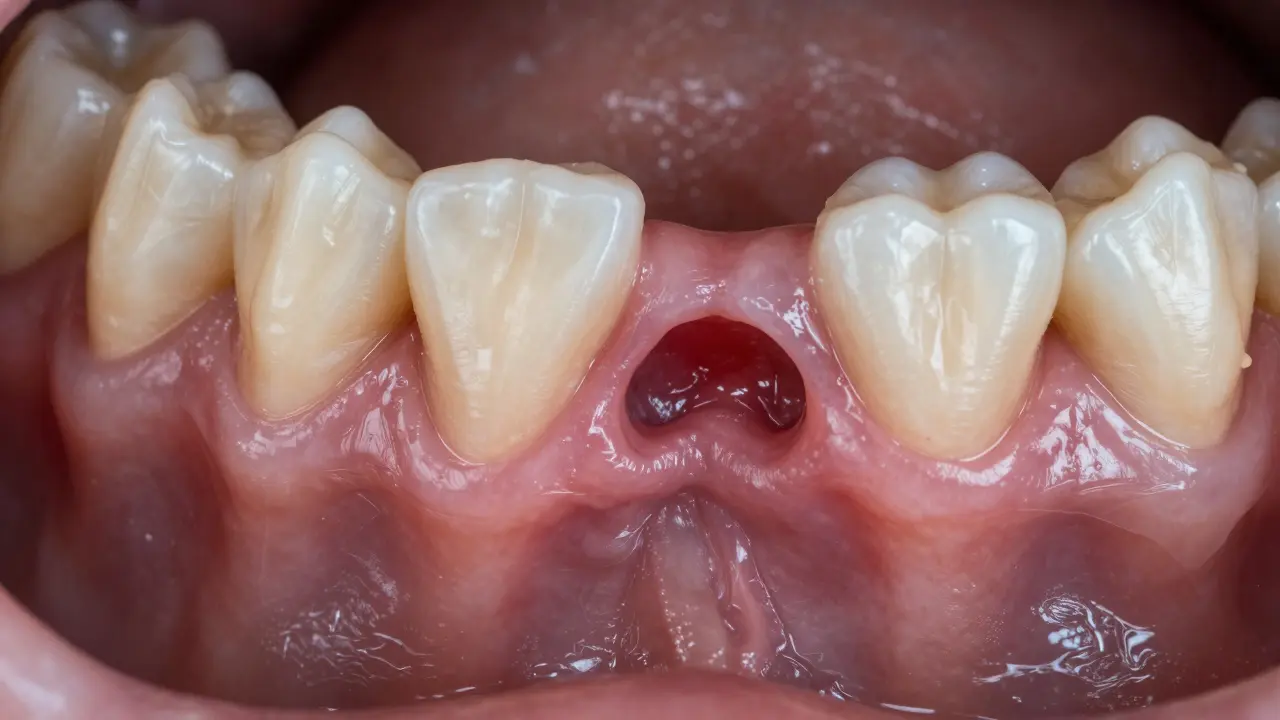

Co je kyretáž zubů a kdy je potřeba?

Kyretáž zubů je hluboké čištění pod dásní při parodontitidě. Zabraňuje ztrátě zubů a ničení kosti. Víte, kdy ji potřebujete a co dělat po léčbě?